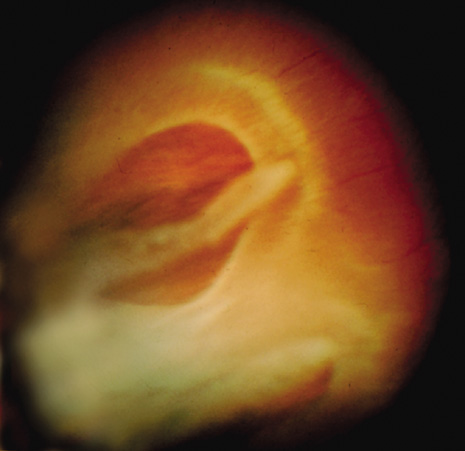

The presence of a bridging vessel over the retinal tear can be problematic (Fig. 8). During the procedure further tension on a bridging vessel can lead to vitreous hemorrhage and loss of visualization. Cryotherapy applied to the bridging vessel first can sometimes help to minimize the bleeding, but manipulation of the probe prior to the application can result in rupture of the blood vessel. Careful placement of the probe and quick cryotherapy application to the bridging vessel is advised. Laser applied to a retinal tear with a bridging vessel should be placed furthest away from the vessel and approaching the vessel last. Laser can be applied onto the distal and proximal portion of the vessel, but treatment to the bridging portion of the vessel should be avoided. Sometimes bleeding occurs despite precautions, and if visualization is dramatically reduced, careful observation is warranted. Further surgical intervention may be necessary if insufficient treatment was performed prior to the vitreous hemorrhage.

Fig. 8. Retinal tear with a small bridging vessel.